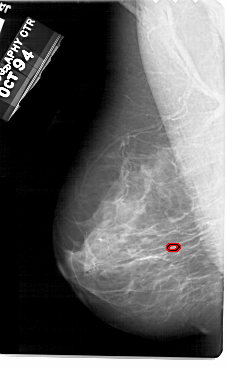

A_1945_1.RIGHT_MLO

RIGHT_MLO LINES 5491 PIXELS_PER_LINE 3046 BITS_PER_PIXEL 12 RESOLUTION 43.5 NON_OVERLAY

RIGHT_CC LINES 5491 PIXELS_PER_LINE 3031 BITS_PER_PIXEL 12 RESOLUTION 43.5 NON_OVERLAY